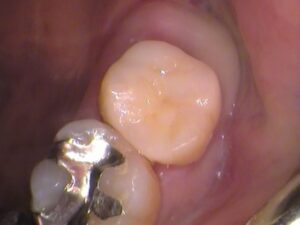

虫歯を全部とると、

このような状態です。

検知液で染まらないところまできました。

内部は健康な黄色い象牙質が見えています。

歯の神経までは達しませんでしたので、

神経の治療はしなくて済みました。